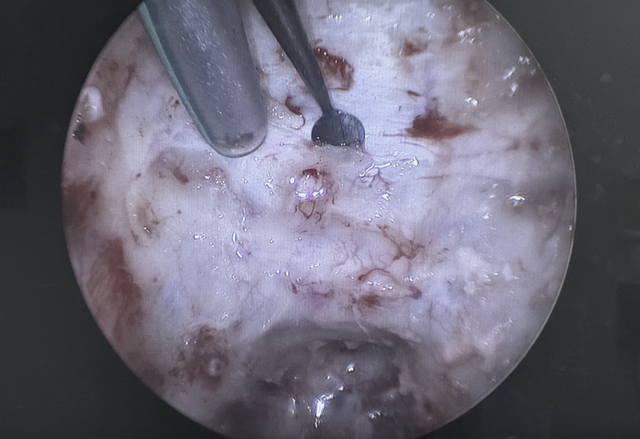

这是一台脑动脉瘤手术,通过术前影像、术中精细梳理,很快找到了动脉瘤,再通过多次的试夹闭,保留了穿支血管。